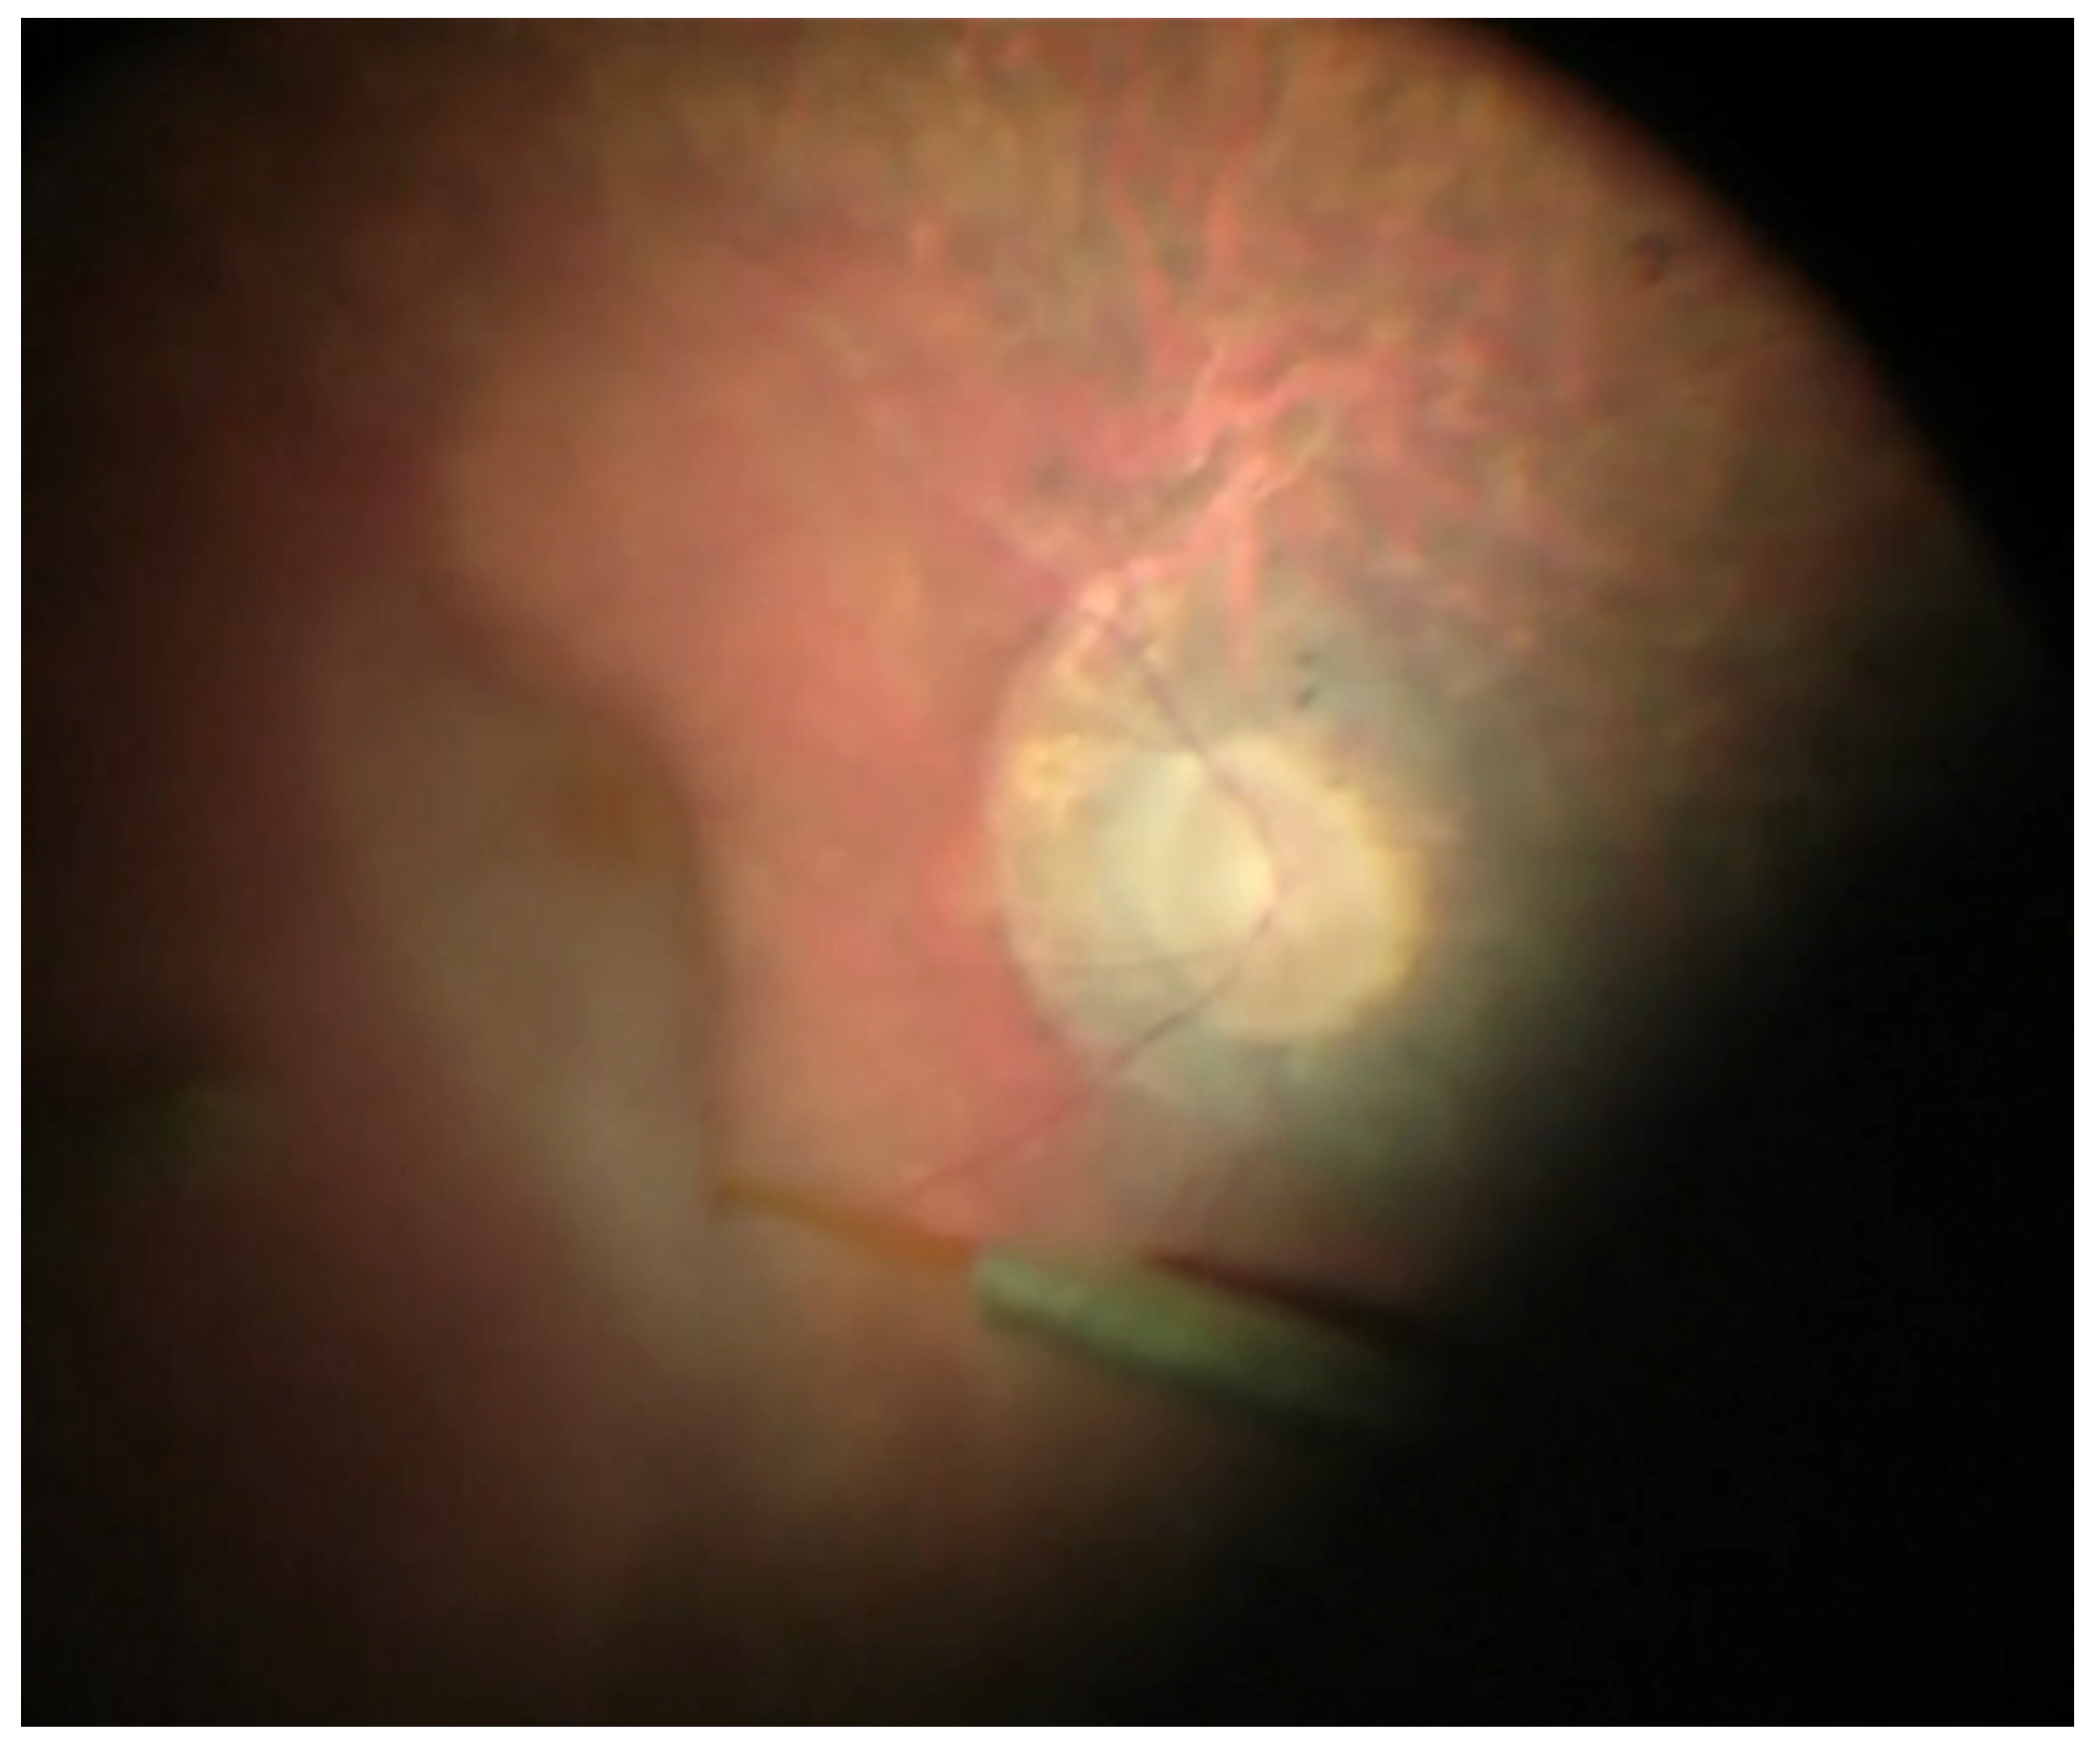

Surgical Technique